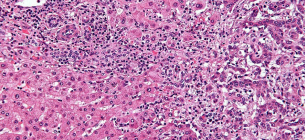

желчевыводящие пути